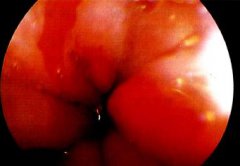

食管下段的鱗狀上皮被柱狀上皮覆蓋,因為英國人Barrett首先報道,因此稱 Barrett食管 ,中文翻譯為巴雷特食管。目前認為是獲得性,可能與 反流性食管炎 相關(guān),并有發(fā)生 腺癌 的可能。其癥狀...